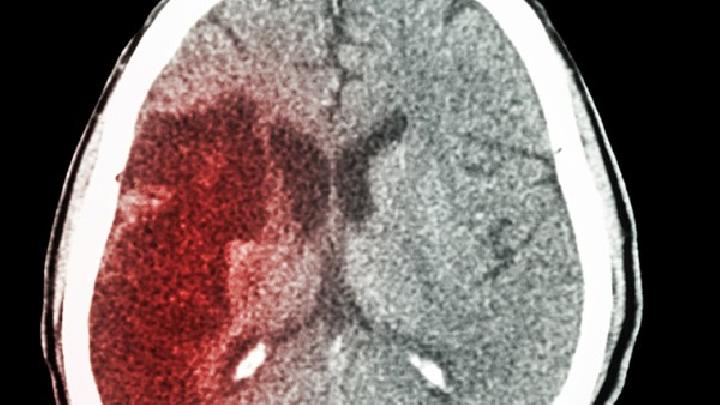

随着年龄的增长,身体和器官也相对较老。他们一生都在努力工作。过度工作和积累工作是一种常见现象。许多人不可避免地患有不同程度的慢性病,如动脉硬化、脑栓塞、脑出血、糖尿病和高血压。大量临床病例研究表明,这些疾病是脑萎缩和痴呆症的罪魁祸首,这些慢性病长期无法治愈,而且越来越严重。一些老年人固执。只要他们能走路,他们就认为自己没有疾病。他们拒绝劝说和治疗,病情进一步恶化。最终导致脑动脉退行性病变、脑神经细胞缺血、缺氧和变性坏死,导致脑萎缩和痴呆。

6.脑血管疾病。脑血管疾病可导致脑组织损伤,脑组织损伤未及时治疗或常规治疗,后期可能导致脑萎缩。